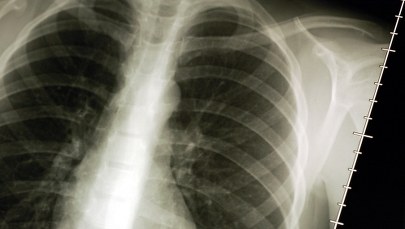

"Joe Cocker przegrał walkę z rakiem płuc" - takie tytuły smutnej informacji o śmierci wybitnego muzyka budzą mój sprzeciw. Nie tylko w jego przypadku zresztą. Jest w nich coś dodatkowo stygmatyzującego zmarłego, który nie tylko zmarł, ale i przy okazji "przegrał". Choć wszyscy wiemy, co takie sformułowanie dokładnie oznacza, budzi dodatkowe, niepotrzebne, negatywne skojarzenia.